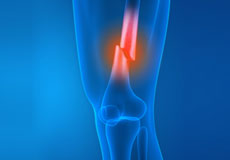

Knee Pain

Knee pain is a common condition affecting individuals of various age groups. It not only affects movement but also impacts your quality of life. An injury or disease of the knee joint or any structure surrounding the knee can result in knee pain.